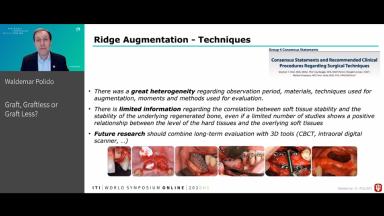

This congress lecture will address a common issue in implant dentistry: bone deficiency in patients. Clinicians often need to explain graft options to improve outcomes. While bone grafting leads to ideal dentoalveolar reconstruction, it's invasive, costly, and demands high expertise. Alternatively, graftless methods like tilted, short, or narrow implants offer a way to avoid grafting but may have biological or mechanical limitations and aren't suitable for all patients. Advances in digital planning, biomaterials, and implant design now allow for minimal grafting, targeting specific sites for smaller volume bone reconstruction. These methods are more predictable and provide better bone support and implant positioning.

This presentation will examine these strategies through clinical examples, focusing on patient-oriented solutions.